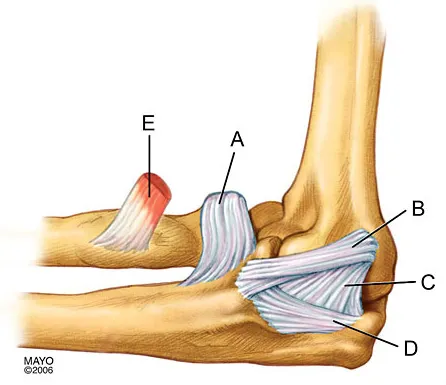

Question 21High Yield

In Figure 2, which of the following structures is the primary stabilizer in preventing valgus instability of the elbow?

Explanation